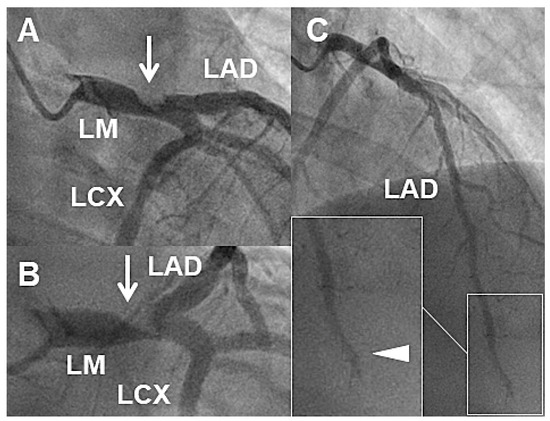

Case 1

Case 2